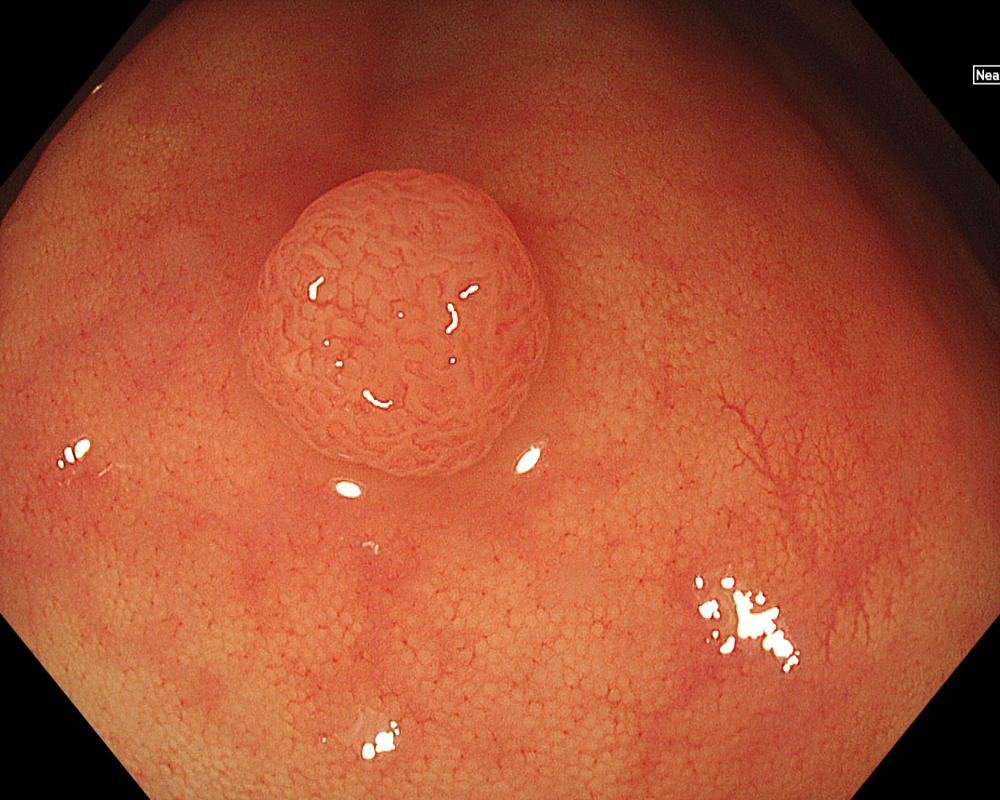

Next, initiate observation by approaching the lesion. As mentioned, the CF-EZ1500D scope allows proximity up to approximately 3 mm even in normal mode. Switching to Near focus mode with a single button press allows for observation up to 1.5 mm. EDOF facilitates easy focusing on both near and far distances, making it possible to continuously capture images that are sharply in focus across the entire screen, even for lesions with uneven surfaces or those with motion due to respiratory variation. Observation under water is useful if halation is a concern or if more detailed observation is desired.

In addition to eliminating halation, underwater observation has a magnification effect. When combined with the Near focus mode, it allows for even clearer magnified images. For determining the indication for CSP, the JNET (Japan NBI Expert Team) classification is used, which evaluates the surface Vessel pattern and Surface pattern using NBI + Near focus magnified observation. If the lesion is classified as Type 2A (characterized by a regular caliber and regular distribution (meshed/spiral pattern) in the Vessel pattern, and a regular pattern (tubular/branched/papillary) in the Surface pattern), it is highly likely to be a lowgrade intramucosal neoplasia, and CSP can be indicated if the size is less than 10 mm. If the lesion is classified as Type 2B (characterized by variable caliber and irregular distribution in the Vessel pattern, and an irregular or obscure pattern in the Surface pattern), there is a higher possibility of high-grade intramucosal neoplasia or deeper invasion. Indiscriminately performing CSP based solely on small size should be avoided in these cases.